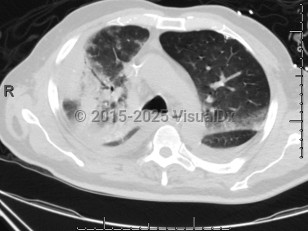

Chlamydophila pneumoniae pneumonia

Chlamydophilia pneumoniae (also known as Chlamydia pneumoniae) is an obligate intracellular bacterium that causes pneumonia.

Transmission of this infection is thought to occur through respiratory droplets, and institutional outbreaks have been reported. Serologic studies have revealed that many adolescents and most adults are seropositive.

Associations between C. pneumoniae infection and asthma, atherosclerosis, and other chronic conditions have been reported, but the data are not conclusive.